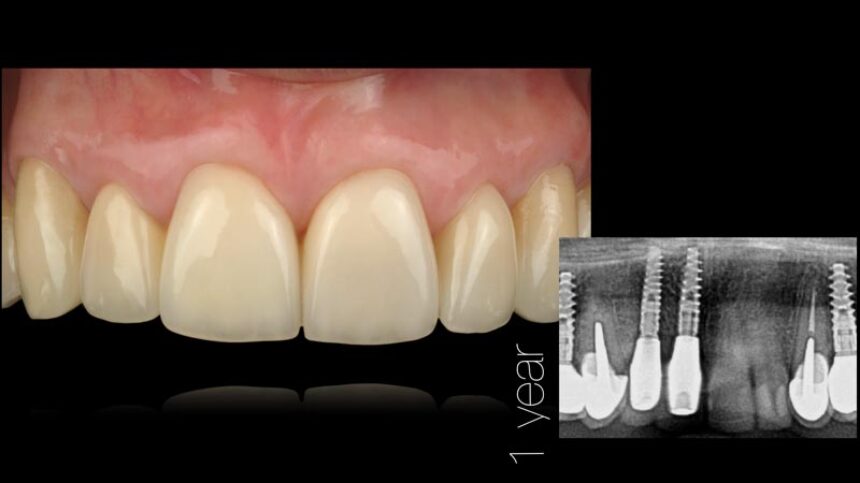

The congress will also feature Dr. Iñaki Gamborena whose lectures will focus on the key factors affecting the success of treatment in the aesthetic zone, both in patients with a purely dental arch and in implant restorations. His presentations will include the surgical and the prosthetic management of these cases, and he will also elaborate on the management of complex cases with past failures.

Aesthetic Implant Dentistry – basic science

Anatomical determinants of aesthetic implant restoration – Diagnosis and treatment planning.

Soft Tissue management.

Surgical techniques for hard and soft tissue augmentation.

Understand the importance of CTG around dental implants for long term results

Techniques and tools to ensure predictable surgical & prosthetic results